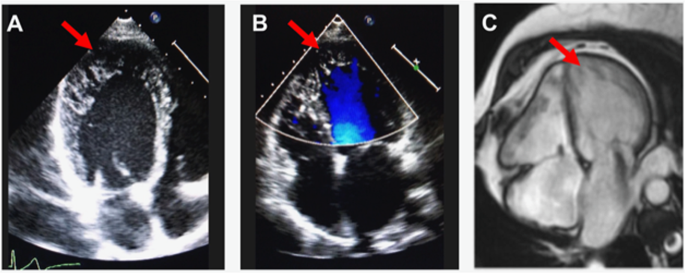

Confirmatory diagnoses were made by experienced cardiologists based on clinical presentation and interpretation of echocardiogram and cardiac magnetic resonance imaging results (Fig. 1) using the Jenni and Petersen criteria, respectively7,8. Past clinical data were retrospectively retrieved from medical records: clinical assessment included physical examination, 12-lead electrocardiogram (ECG), and echocardiogram. LV systolic dysfunction was defined as a systolic left ventricular ejection fraction (LVEF) < 50% on echocardiogram. Cardiac magnetic resonance imaging results were available for the majority of the patients. The patients were also assessed for any syndromic features, including pectus excavatum and upper limb abnormalities.

Left ventricular non-compaction from a representative subject from the study, on a, 2D-transthoracic echocardiogram, b, 2D-transthoracic echocardiogram with colour Doppler flow, and c, cardiac magnetic resonance imaging. Red arrows indicate regions of non-compaction.